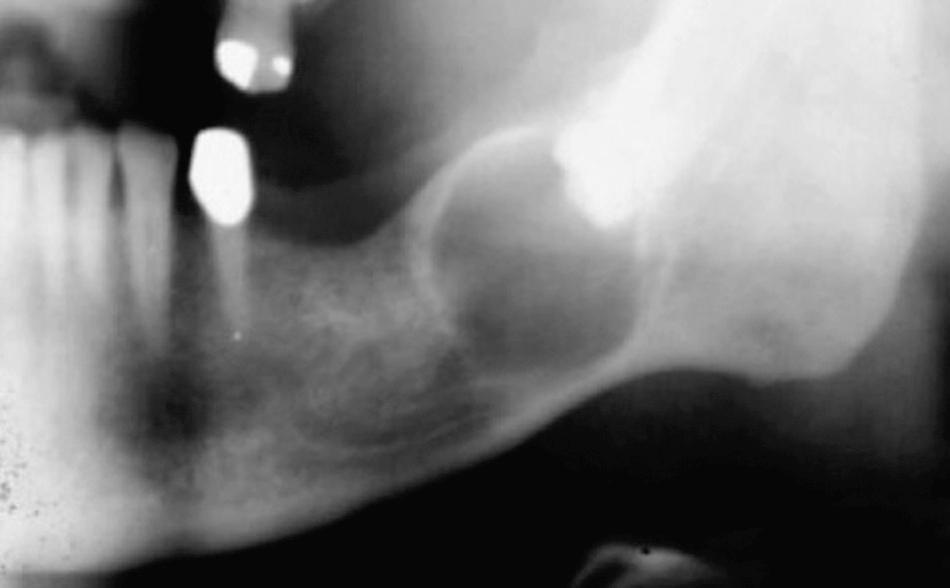

When impacted teeth are completely within the alveolar process, the associated follicular sac is also frequently retained. Although the dental follicle maintains its original size in most patients, it may undergo cystic degeneration and become a dentigerous cyst. If the patient is closely monitored, the dentist can diagnose the cyst before it reaches large proportions ( Fig. 10.11 ). However, unmonitored cysts can reach enormous sizes ( Fig. 10.12 ). As a general guideline, if the follicular space around the crown of the tooth is greater than 3 mm, the preoperative diagnosis of a dentigerous cyst is reasonable.

Fig. 10.11, Small dentigerous cyst arising around an impacted tooth.

Fig. 10.12, Large dentigerous cyst that extends from the coronoid process to the mental foramen. The cyst has displaced the impacted third molar to the inferior border of the mandible.